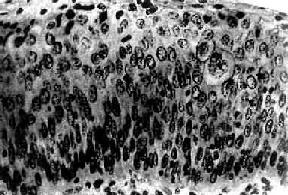

图13-3 子宫颈原位癌

癌变限于上皮层内,细胞核肥大、深染,大小不一,形态不规则,核仁明显,核分裂像易见,且见巨细胞(右侧上方),这种细胞间变累及上皮全层,但基底膜完整,癌细胞未浸润到基底膜下间质